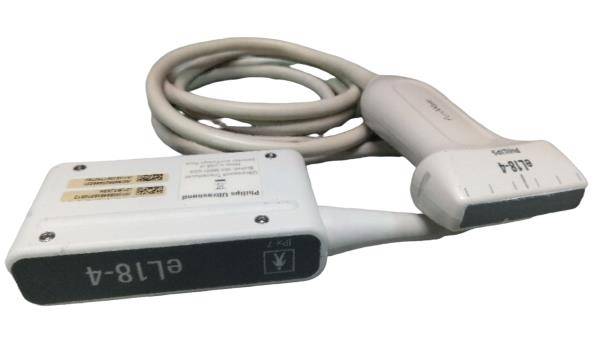

standard Probe: convex transvaginal 2 probes

Option probe: linear / Rectal probe

The portable ultrasound scanner is an essential tool for various medical environments. It offers the flexibility to conduct scans in clinics, hospitals, and even at home. Doctors and healthcare professionals appreciate its compact design, which facilitates ease of transport. Furthermore, the inclusion of both convex and transvaginal probes expands its usability, allowing practitioners to perform different types of examinations efficiently.